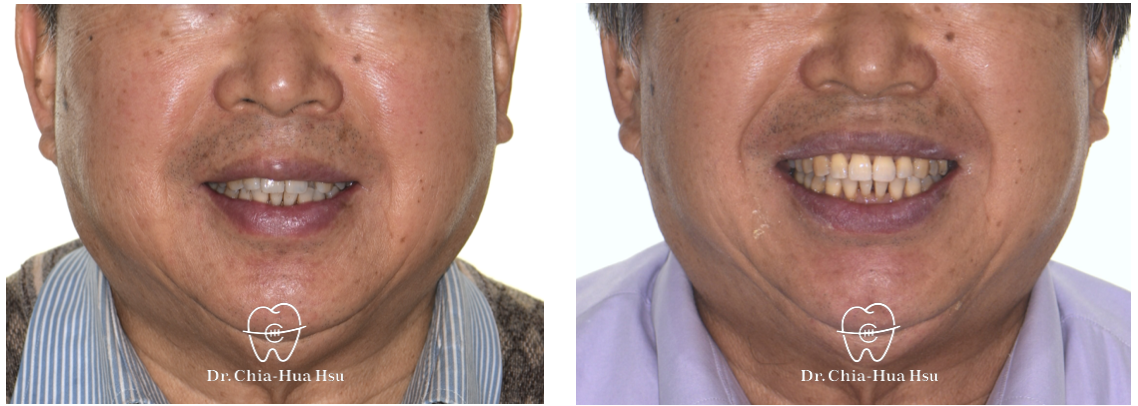

治療前

治療後